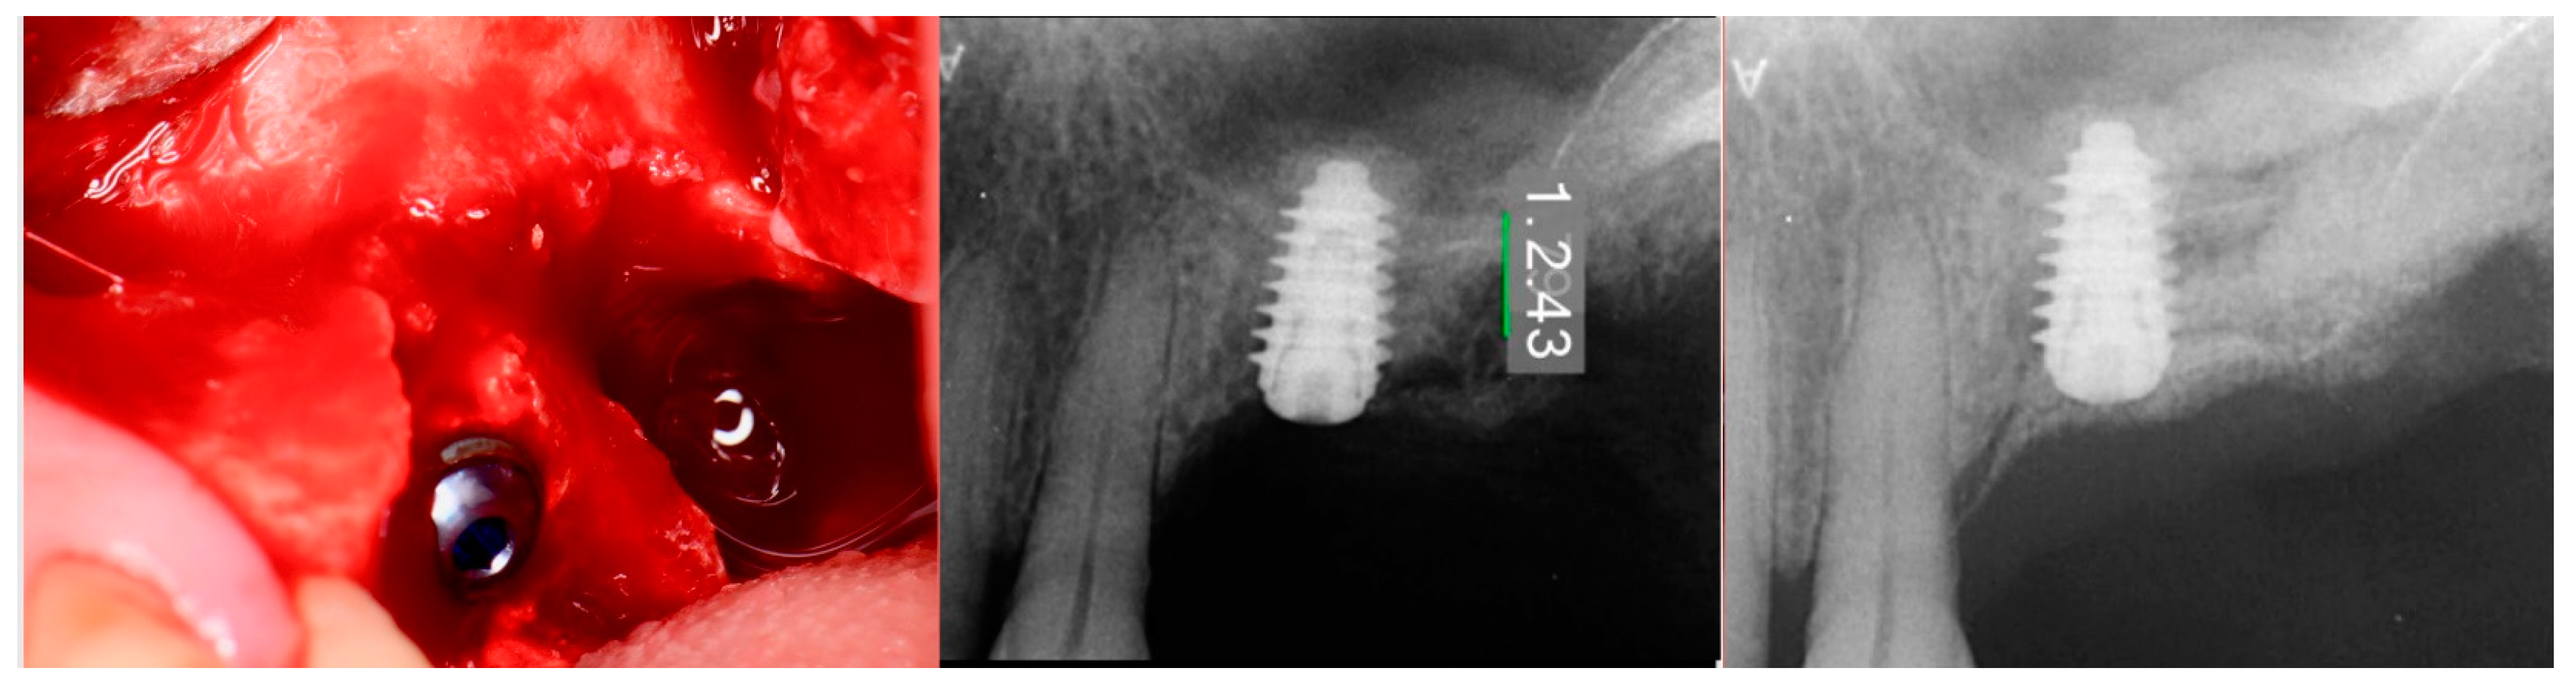

The patient returned at 10-weeks implant and graft placement and the soft tissue over the posterior quadrant was noted to be healed with no inflammation present (Figure 10 left). Following local anesthetic administration a full thickness flap was elevated and the previously grafted 2nd molar crestal area was filled with immature host bone (Figure 10 right). A radiograph was obtained, which noted a crestal height of 7.1 mm present (Figure 11 left). The 2nd molar site was prepared in a similar fashion as previously detailed, utilizing Densah burs to osseodensify the area and accomplish a crestal sinus augmentation and a 5 × 8.5 mm Anyridge implant was placed (Figure 11 middle and right). An impression of the 1st molar implant was obtained to initiate its restoration while the 2nd molar implant was integrating. A healing abutment was placed on the implant at the 1st molar and a cover screw on the 2nd molar implant and a radiograph obtained to document the clinical result to date (Figure 12).

Figure 10.

The keratinized gingiva at 10 weeks post-surgery (left) and following flap of the site demonstrating conversion of the osseous graft at the 2nd molar site that will allow implant placement at that site (right).

Figure 11.

Radiograph demonstrating sufficient height of the ridge to allow primary stability of an implant placed at the 2nd molar with a crestal sinus augmentation at 10 weeks of graft healing (left), site preparation for the crestal sinus augmentation (middle) and implant placement into the site (right). Green line is the measurement of the height of the bone at that point between the crest and the sinus floor.